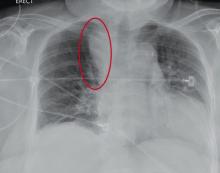

Radiograph of preoperative patient after fall.

Chest radiograph of preop patient with acute left subdural hematoma after ground level fall.

You are doing preoperative orders on a patient scheduled for surgery tomorrow morning. The patient is a 75-year-old woman who was admitted with an acute left subdural hematoma after sustaining a ground-level fall. Her medical history is significant for hypertension and diabetes. Social history is unremarkable. She is neurologically intact except for occasional confusion and aphasia. She moves all her extremities well. As you review her lab results, one of the nurses mentions that the radiology department called about “something abnormal” on the patient’s chest radiograph. You pull up the patient’s portable chest radiograph on the computer to review. What is your impression?

The radiograph demonstrates a fairly large (4 x 6 cm) right paratracheal mass of unclear etiology. This type of finding warrants further evaluation with contrasted CT.

Fortunately for this patient, a subsequent study demonstrated a slightly enlarged thyroid gland. This correlated with the radiographic

finding.